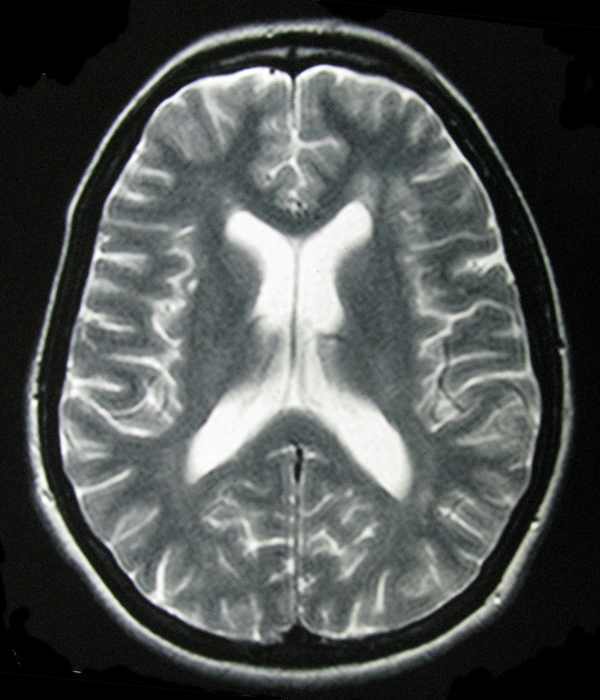

- My Brain in 2009